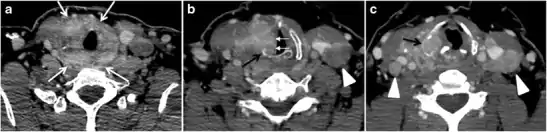

Fig. 5. A poorly differentiated invasive left thyroid mass in a 58-year-old female patient. a Sagittal greyscale neck ultrasound shows a large hypoechoic lesion with macro-calcification and micro-calcification. b Sagittal colour Doppler ultrasound shows left internal jugular vein filling defect with detected internal vascularity suggestive of tumour thrombus. c Enhanced axial and coronal CT scans of the neck show heterogeneously enhancing large lesion replacing the left thyroid lobe and extending to the isthmus and the medial aspect of the right thyroid lobe (white arrow). The mass and the conglomerate lymph nodes measure 12.5 × 7 × 5.8 cm (white arrows). d, e Axial enhanced CT scans show enlarged left cervical nodes (white arrow) and left internal jugular vein (IJV) thrombus (black arrows). Note the IJV distention and central enhancing portion in the upper cut (black arrow in e) concerning the tumour thrombus. f, g Enhanced axial CT scan of the upper chest demonstrate a mass extension into the retrosternal area, left tracheoesophageal groove, and posterior to the trachea (white arrows in f). There are multiple bilateral pulmonary nodules (white arrows in g).[1]

Surgery is the primary mode of treatment for DTCs. Post total thyroidectomy radioactive iodine (RAI) ablation is an option, especially in patients with distant metastasis, tumours larger than 4 cm, or extra-thyroidal disease extension. Ultrasound examination is usually adequate in evaluating primary tumours and cervical lymph nodes. Preoperative cross-sectional imaging with CT or MRI is indicated if there is a concern for local invasion that may alter the patient's staging as well as surgical approach (Figs. 4, 55 and 6)6) . Some thyroid primaries may be small, diffuse, or multifocal and therefore may be occult on imaging (Fig. 4) .[1]

The radiologist must evaluate the central structures draping the thyroid gland including the trachea, oesophagus, larynx, and pharynx, as well as the recurrent laryngeal nerve. Invasion is suspected if the thyroid mass abuts the airway or oesophagus for more than 180 degrees. Luminal deformity, mucosal thickening and mucosal focal irregularity are more specific indicators of invasion. Obliteration of the fat planes of the tracheoesophageal groove in three axial images and signs of vocal cord paralysis are indicative of recurrent laryngeal nerve invasion. Invasion of these central structures meets the criteria for T4a disease (Figs. 5 and and6)6).[1]

Arterial invasion constitutes T4b disease, which may preclude curative surgery. More than 180 degrees of arterial encasement is suggestive of invasion, however, arterial deformity or narrowing is much more suspicious for invasion. The carotid artery is the most commonly involved artery; however, the mediastinal vessels should also be examined. Encasement of the carotid artery or mediastinal vessels for more than 270 degrees is unlikely to be resectable. On the other hand, occlusion or effacement of the internal jugular vein can occur without invasion and does not influence surgical resectability or staging. Asymmetry of the strap muscle and the tumour abutting its external surface are signs of an invasion. However, invasion of the pre-vertebral musculature is more challenging, as a large lesion can compress the muscle without invasion (Figs. 5 and and6)6).[1]

Finally, the possibility of metastatic disease should be excluded. PTCs and medullary thyroid carcinomas tend to metastasize to regional lymph nodes. According to the AJCC/UICC TNM staging system, the nodal stage is classified by site: N1a indicates level VI nodal involvement, including paratracheal nodes; N1b indicates unilateral or bilateral lateral cervical nodal disease or superior mediastinal nodal disease (Figs. 4, 55 and and6)6).[1]

The incidence of hematogenous spread of follicular carcinomas is 21–33 % and that of PTCs is 2–14 %. In medullary thyroid cancer and anaplastic thyroid cancer, distant metastasis was reported in 25% and 40% of patients, respectively. Distant metastases from DTCs tend to have a more favourable prognosis. Distant metastatic disease may appear years after the initial presentation. Therefore, imaging for distant metastases is usually done pre-operatively for anaplastic thyroid cancer and post-operatively for DTCs. DTC distant metastases sites include the lung (50%), bone (25%), lung and bone (20%), followed by other sites (5%).[1]